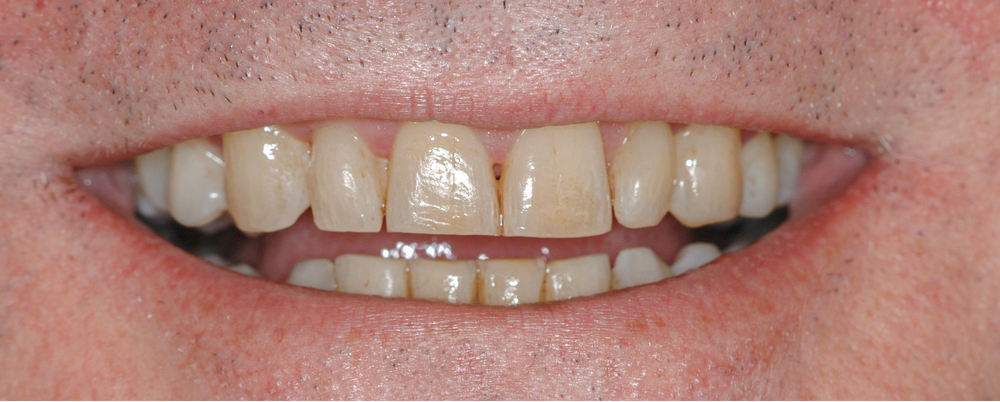

Le patient

- 54 ans

- Parodontite traitée en 2015 stabilisée, puis plusieurs épisodes d’activation sur les dernières années

- Prise en charge de son occlusion par une occlusodontiste et une orthodontiste (durée 3 ans)

- Hygiène orale perfectible

- Sportif et aucune consommation de tabac